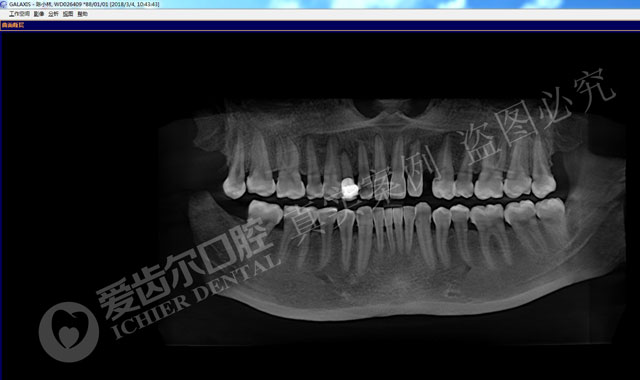

种植前,右上尖牙缺失。

种植中的牙片,种植体与骨组织间紧密贴合

种植后,佩戴牙冠,牙龈无红肿,临牙完好

种植前后对比图